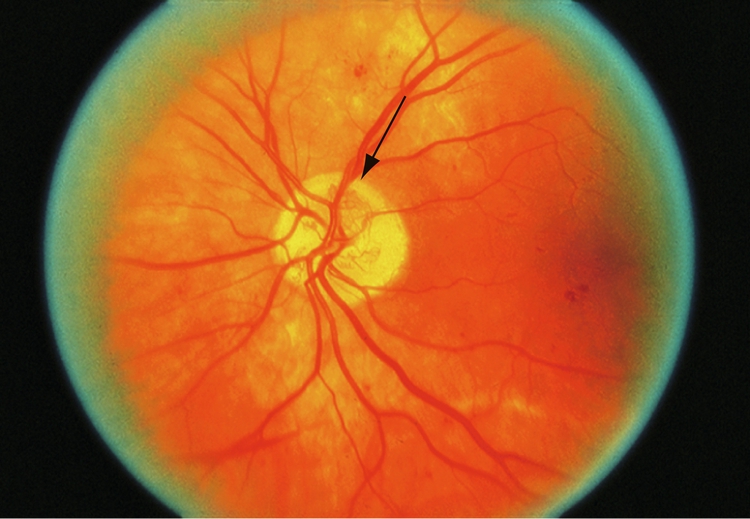

La RDNP sévère a été définie comme ayant une des caractéristiques suivantes :

• hémorragies intrarétiniennes sévères et micro-anévrismes dans les 4 quadrants (fig. 5-7) ;

Figure 5-7

Rétinophotographie montrant des hémorragies diffuses intrarétiniennes (flèche) et des micro-anévrismes dans une rétinopathie diabétique non proliférante (RDNP).

(Photographie standard 2A, avec l'aimable autorisation de l'ETDRS.)